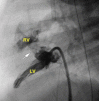

Methods/results: A full-term infant girl (2.9 kg) referred for hypoxia (80% with room air) and murmur was found to have DORV, interrupted inferior vena cava, and restrictive VSD (95-mmHg gradient). Transhepatic access was performed, and an internal mammary (IM) catheter was advanced through the atrial septal defect and into the left ventricle. By transesophageal echocardiographic guidance, a Baylis radiofrequency perforation wire was used to cross the ventricular septum, and the defect was enlarged using a 4-mm cutting balloon. A bare metal stent then was deployed to maintain the newly created VSD. The patient did well after the procedure but required pulmonary artery banding 4 days later. She returned 5 months later with cyanosis and the development of obstructing right ventricle muscle bundles, requiring further surgical palliation.